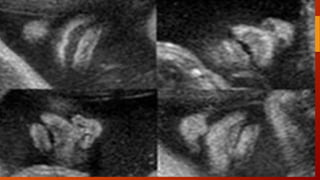

LABIO LEPORINO YFISURA PALATINA • El labio leporino típico aparece como un defecto lineal que se extiende desde el borde superior del labio hasta la fosa nasal Puede estar asociado a fisura palatina, que puede abarcar el paladar blando, el duro, el suelo de la cavidad nasal o incluso el de la órbita. En el 75% de los casos, el defecto es unilateral, y afecta más al lado derecho. • La frecuencia es de 1/800, y en un 50% la alteración aparece de forma asilada (aislada (únicamente labio leporino o fisura palatina) o conjunta. Habitualmente es un hallazgo aislado, pero en un 20% de los casos puede ir asociado a alteraciones genéticas. • Las trisomías 13 y 18 son las más frecuentes. También se ha visto asociado a teratógenos como fármacos antiepilépticos. • El diagnóstico ecográfico se realiza en un corte coronal de la cara, donde en el labio superior se objetiva una zona anecoica, lineal, desde la fosa nasal hasta el labio superior

Para el diagnósticodel paladar hendido se necesitan cortes transversos. Para el diagnóstico del paladar hendido se necesitan cortes transversos.

cortes Corte sagital decara para evaluar perfil del feto. – Morfología de frente, nariz, labios y mentón. Corte coronal (mas importantes), para evaluar integridad facial – A nivel de orbitas para medición de distancia orbitaria – Plano frontocoronal tangencial: nariz, labios, y mentón. Corte transversal: estudio de paladar

Diagnostico Demostrar el surcoo la solución de continuidad a nivel del labio y/o del paladar.  Corte frontocoronal tangencial: imprescindible para el diagnóstico y para establecer bilateralidad.  Corte transversal a nivel del maxilar nos permitirá comprobar la continuidad de los alveolos dentarios y por tanto, descartar o confirmar la presencia de una fisura palatina